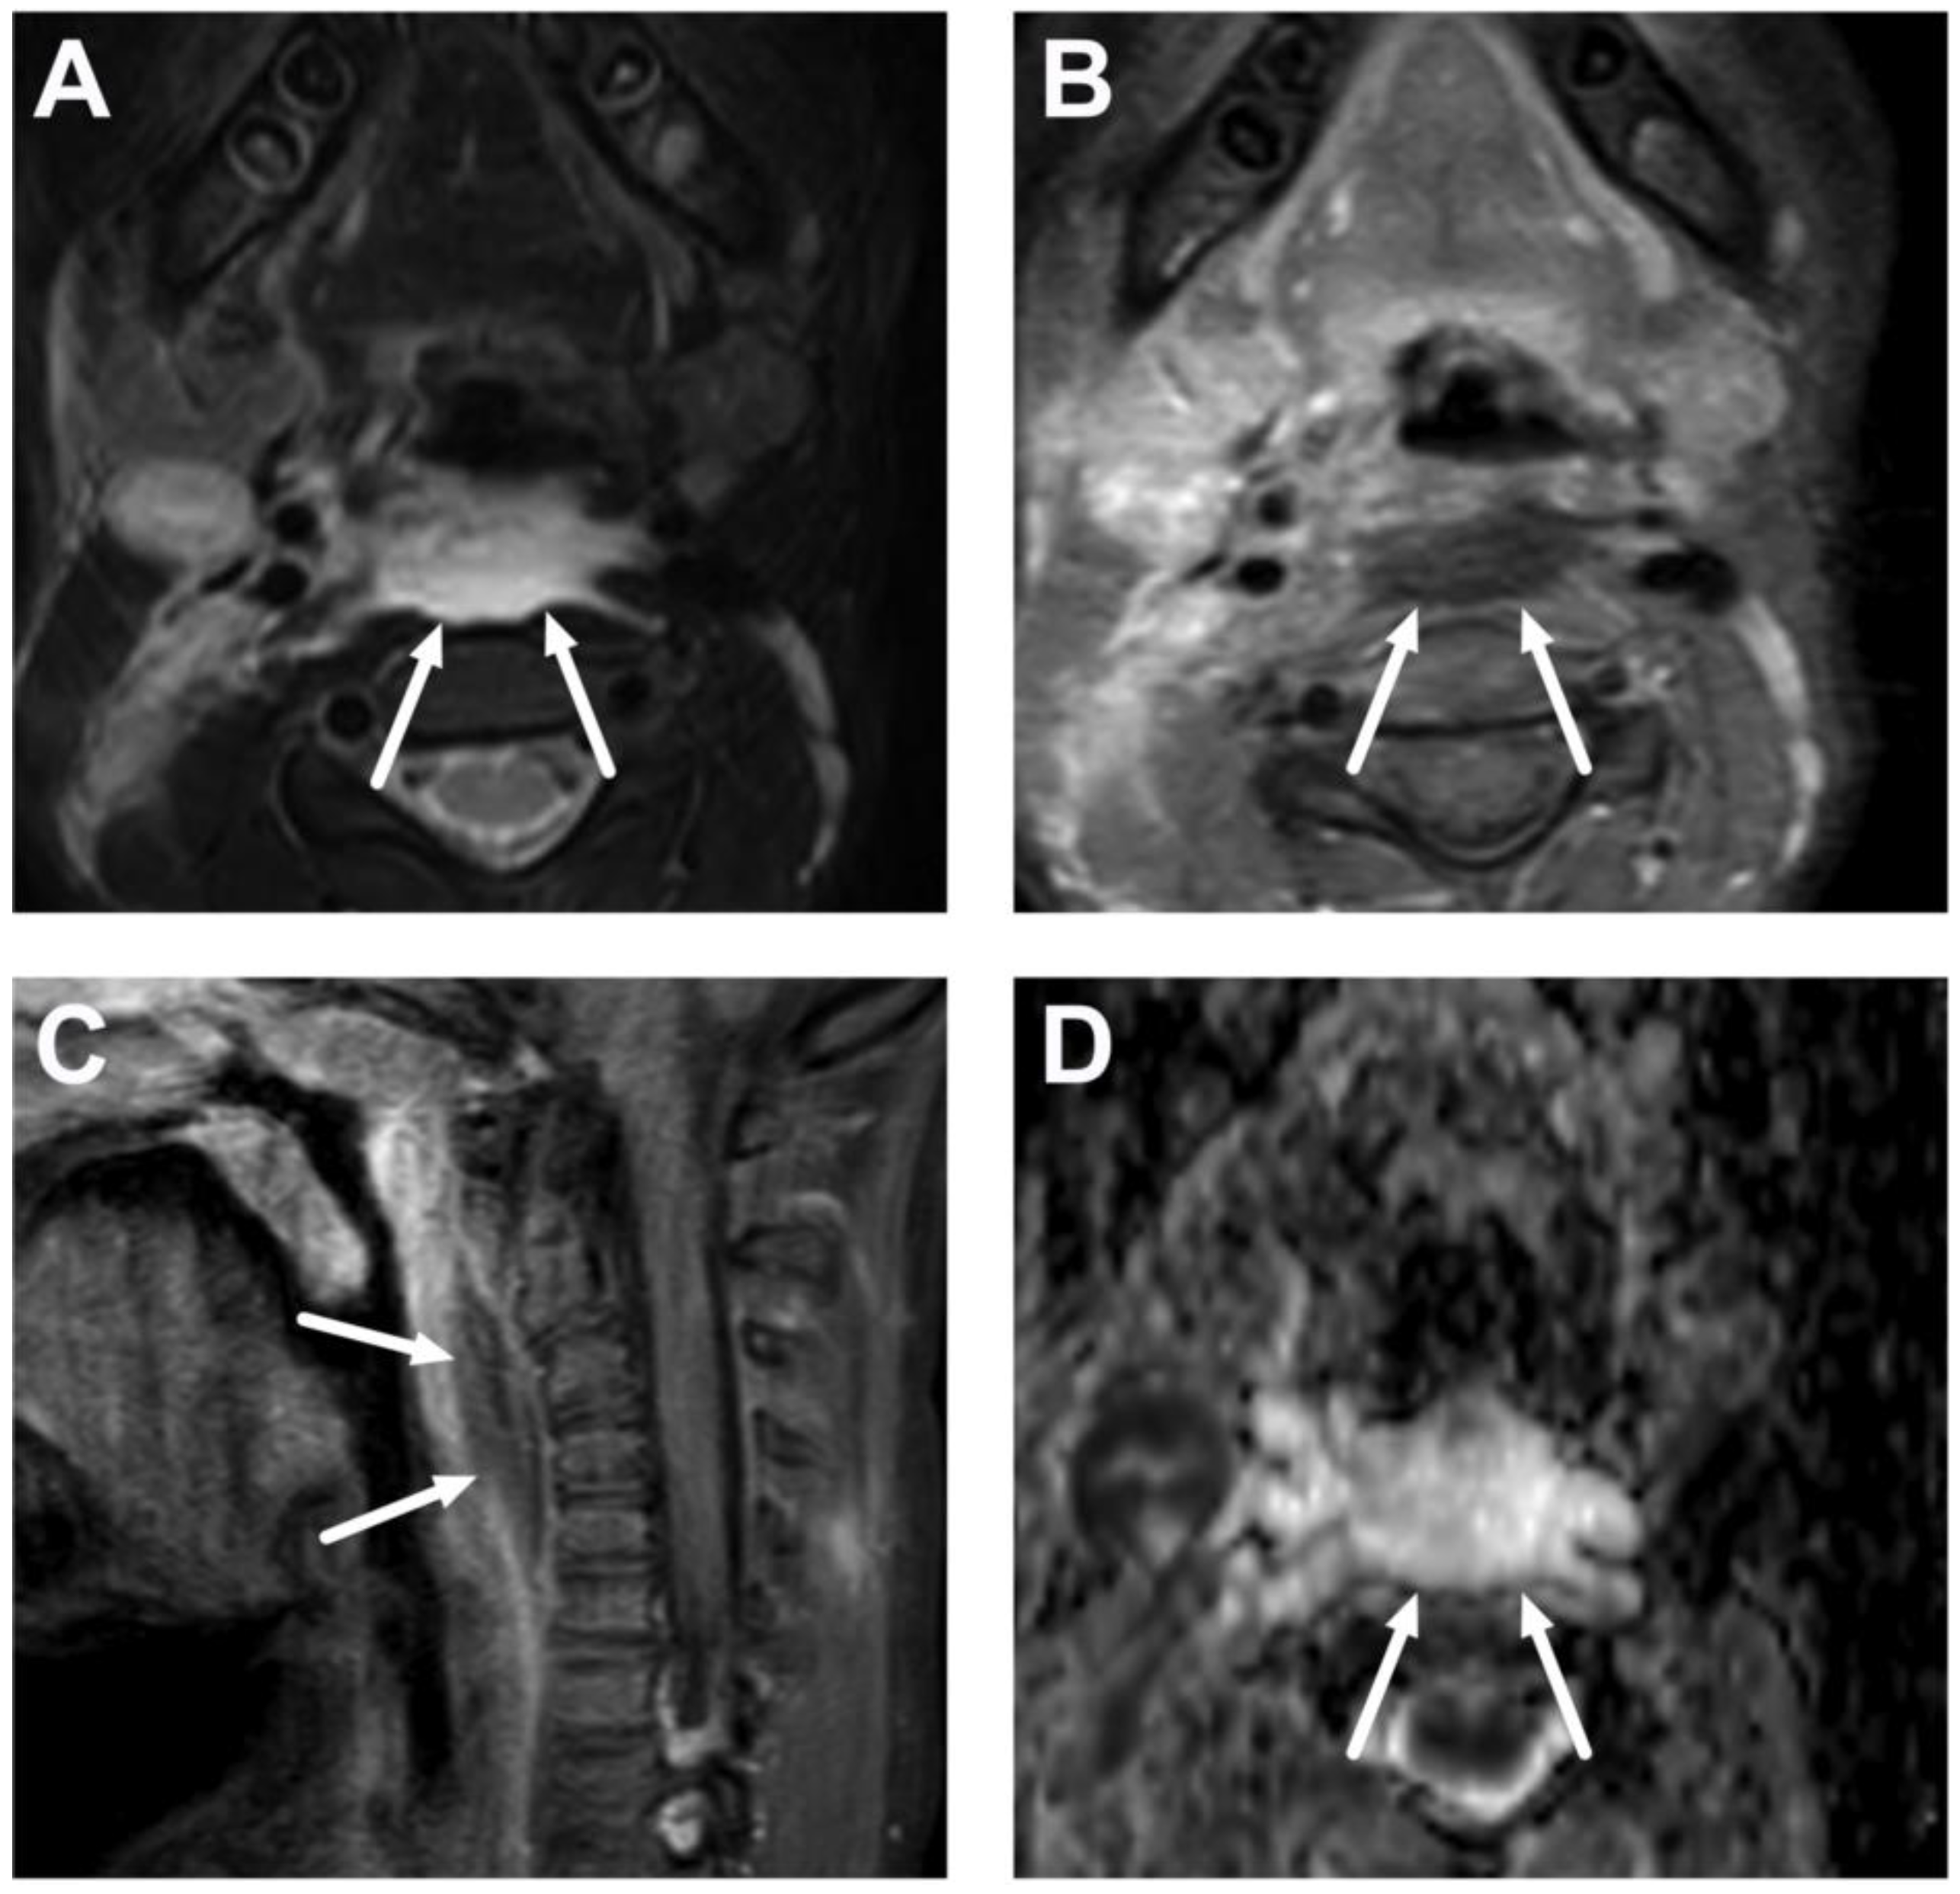

4.2. Retropharyngeal Abscesses and Suppurative Lymphadenitis

6.1. Mediastinitis